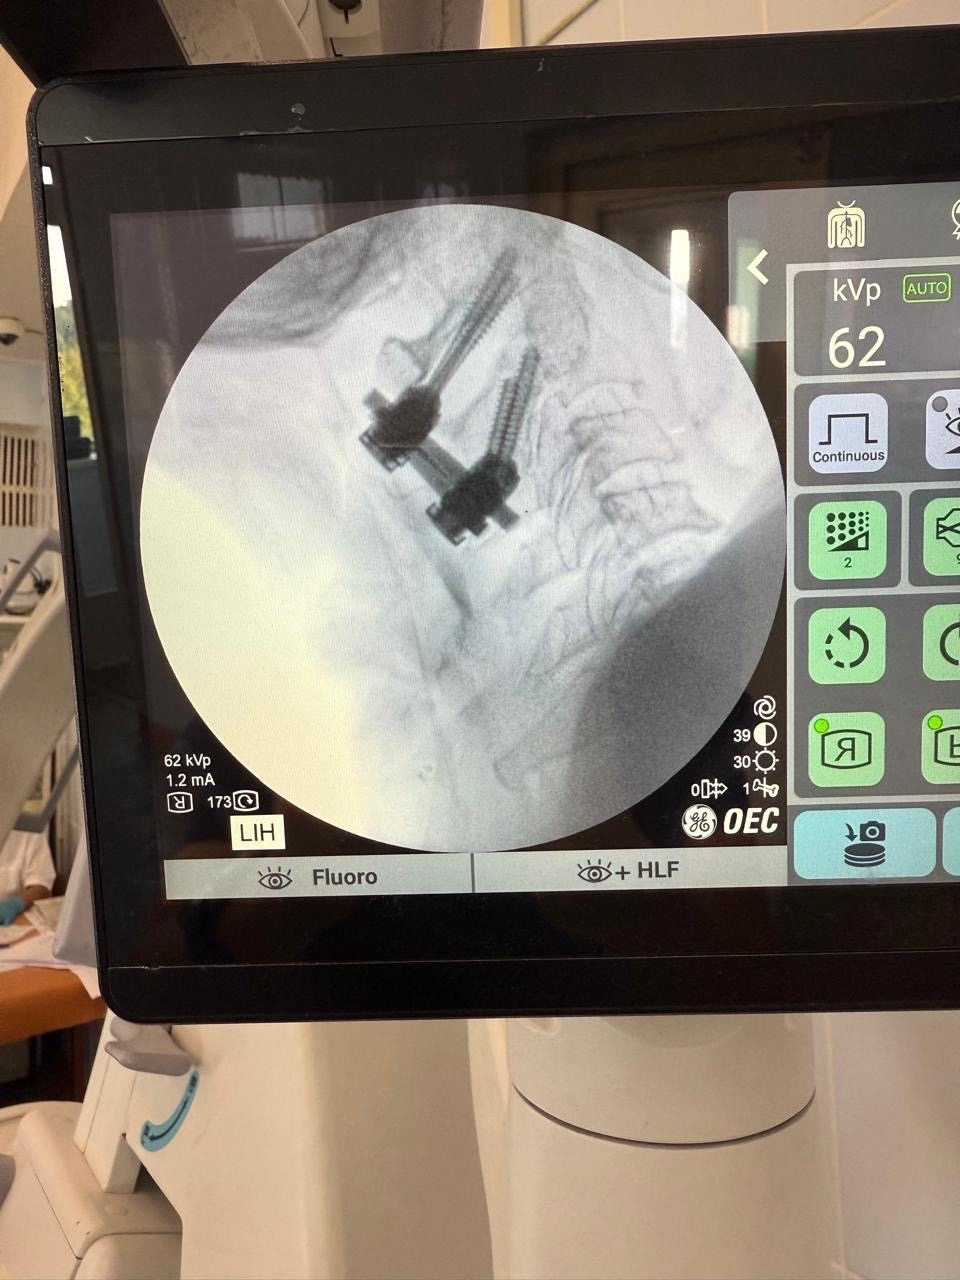

"76-летняя поступила в отделение с перелом зуба осевого позвонка (С2) типа Anderson D’Alonzo II со смещением. Такая травма, полученная в быту, крайне нестабильна и чревата риском повреждения спинного мозга на уровне ствола головного мозга с развитием мгновенного паралича или летального исхода. Консервативное лечение (ношение жесткого воротника) в данном случае было признано недостаточно эффективным из-за высокого риска несращения и постоянной угрозы для жизни. Было принято решение о проведении операции по методике Хармса. Раньше "золотым стандартом" при таких переломах была операция по методике Magerl — транспедикулярная фиксация С1-С2. Однако она технически сложна и сопряжена с риском повреждения позвоночной артерии. Пациентка была выписана в удовлетворительном состоянии под амбулаторное наблюдение. Прогноз — благоприятный, с полным восстановлением качества жизни" - поделился врач-нейрохирург Мухиддин Тохтаров.

Преимущества метода заключаются в высокой стабильности фиксации, меньшем риске повреждения позвоночной артерии по сравнению с классическими методами, возможности применения даже при анатомических аномалиях и ранней активизации пациента — уже на следующий день после операции пациентка могла ходить в специальном ортопедическом воротнике.